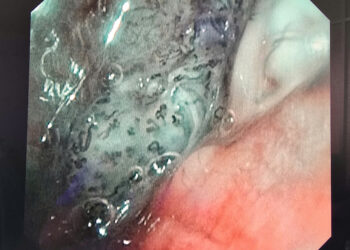

2.3. Quy trình can thiệp mạch vành bằng Stent với giá đỡ tự tiêu:

Giống như quy trình can thiệp mạch vành bằng Stent với giá đỡ Kim loại, tuy nhiên cần tuân thủ chặt chẽ 5 bước như sau:

– Tiến hành nong ĐMV bằng bóng thường nhiều lần với áp lực tăng dần để sao cho tỷ lệ đường kính bóng thường/ ĐMV = 1/1.

– Đo đường kính cũng như chiều dài đoạn ĐMV bị tổn thương sau khi tiêm Nitroglycerin trong lòng ĐMV(0,1-0,2mg).

– Đặt Stent tự tiêu phù hợp về đường kính cũng như chiều dài vào vị trí tổn thương.

– Nong Stent tự tiêu bằng bóng áp lực cao (NC) ít nhất16 bar (sao cho: ĐK Nominal Stent < ĐK bóng NC ≤ ĐK Nominal Stent + 0,5).